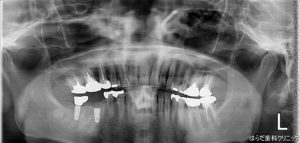

最後にレントゲンを撮影して確認します。

右下(画像では左下)にしっかりとインプラント体が埋入されております。